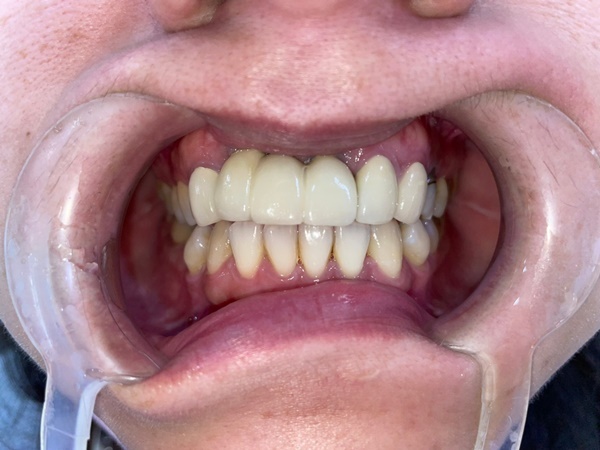

歷時半年的療程

經過朱醫師診斷阿公全口重建植牙傷口恢復情況良好,

這禮拜已經裝上正式假牙

術後阿公說終於可以好好咬蘋果!(歡呼)

看到他安心地吃想吃的東西,終於能放下心中那塊大石頭!